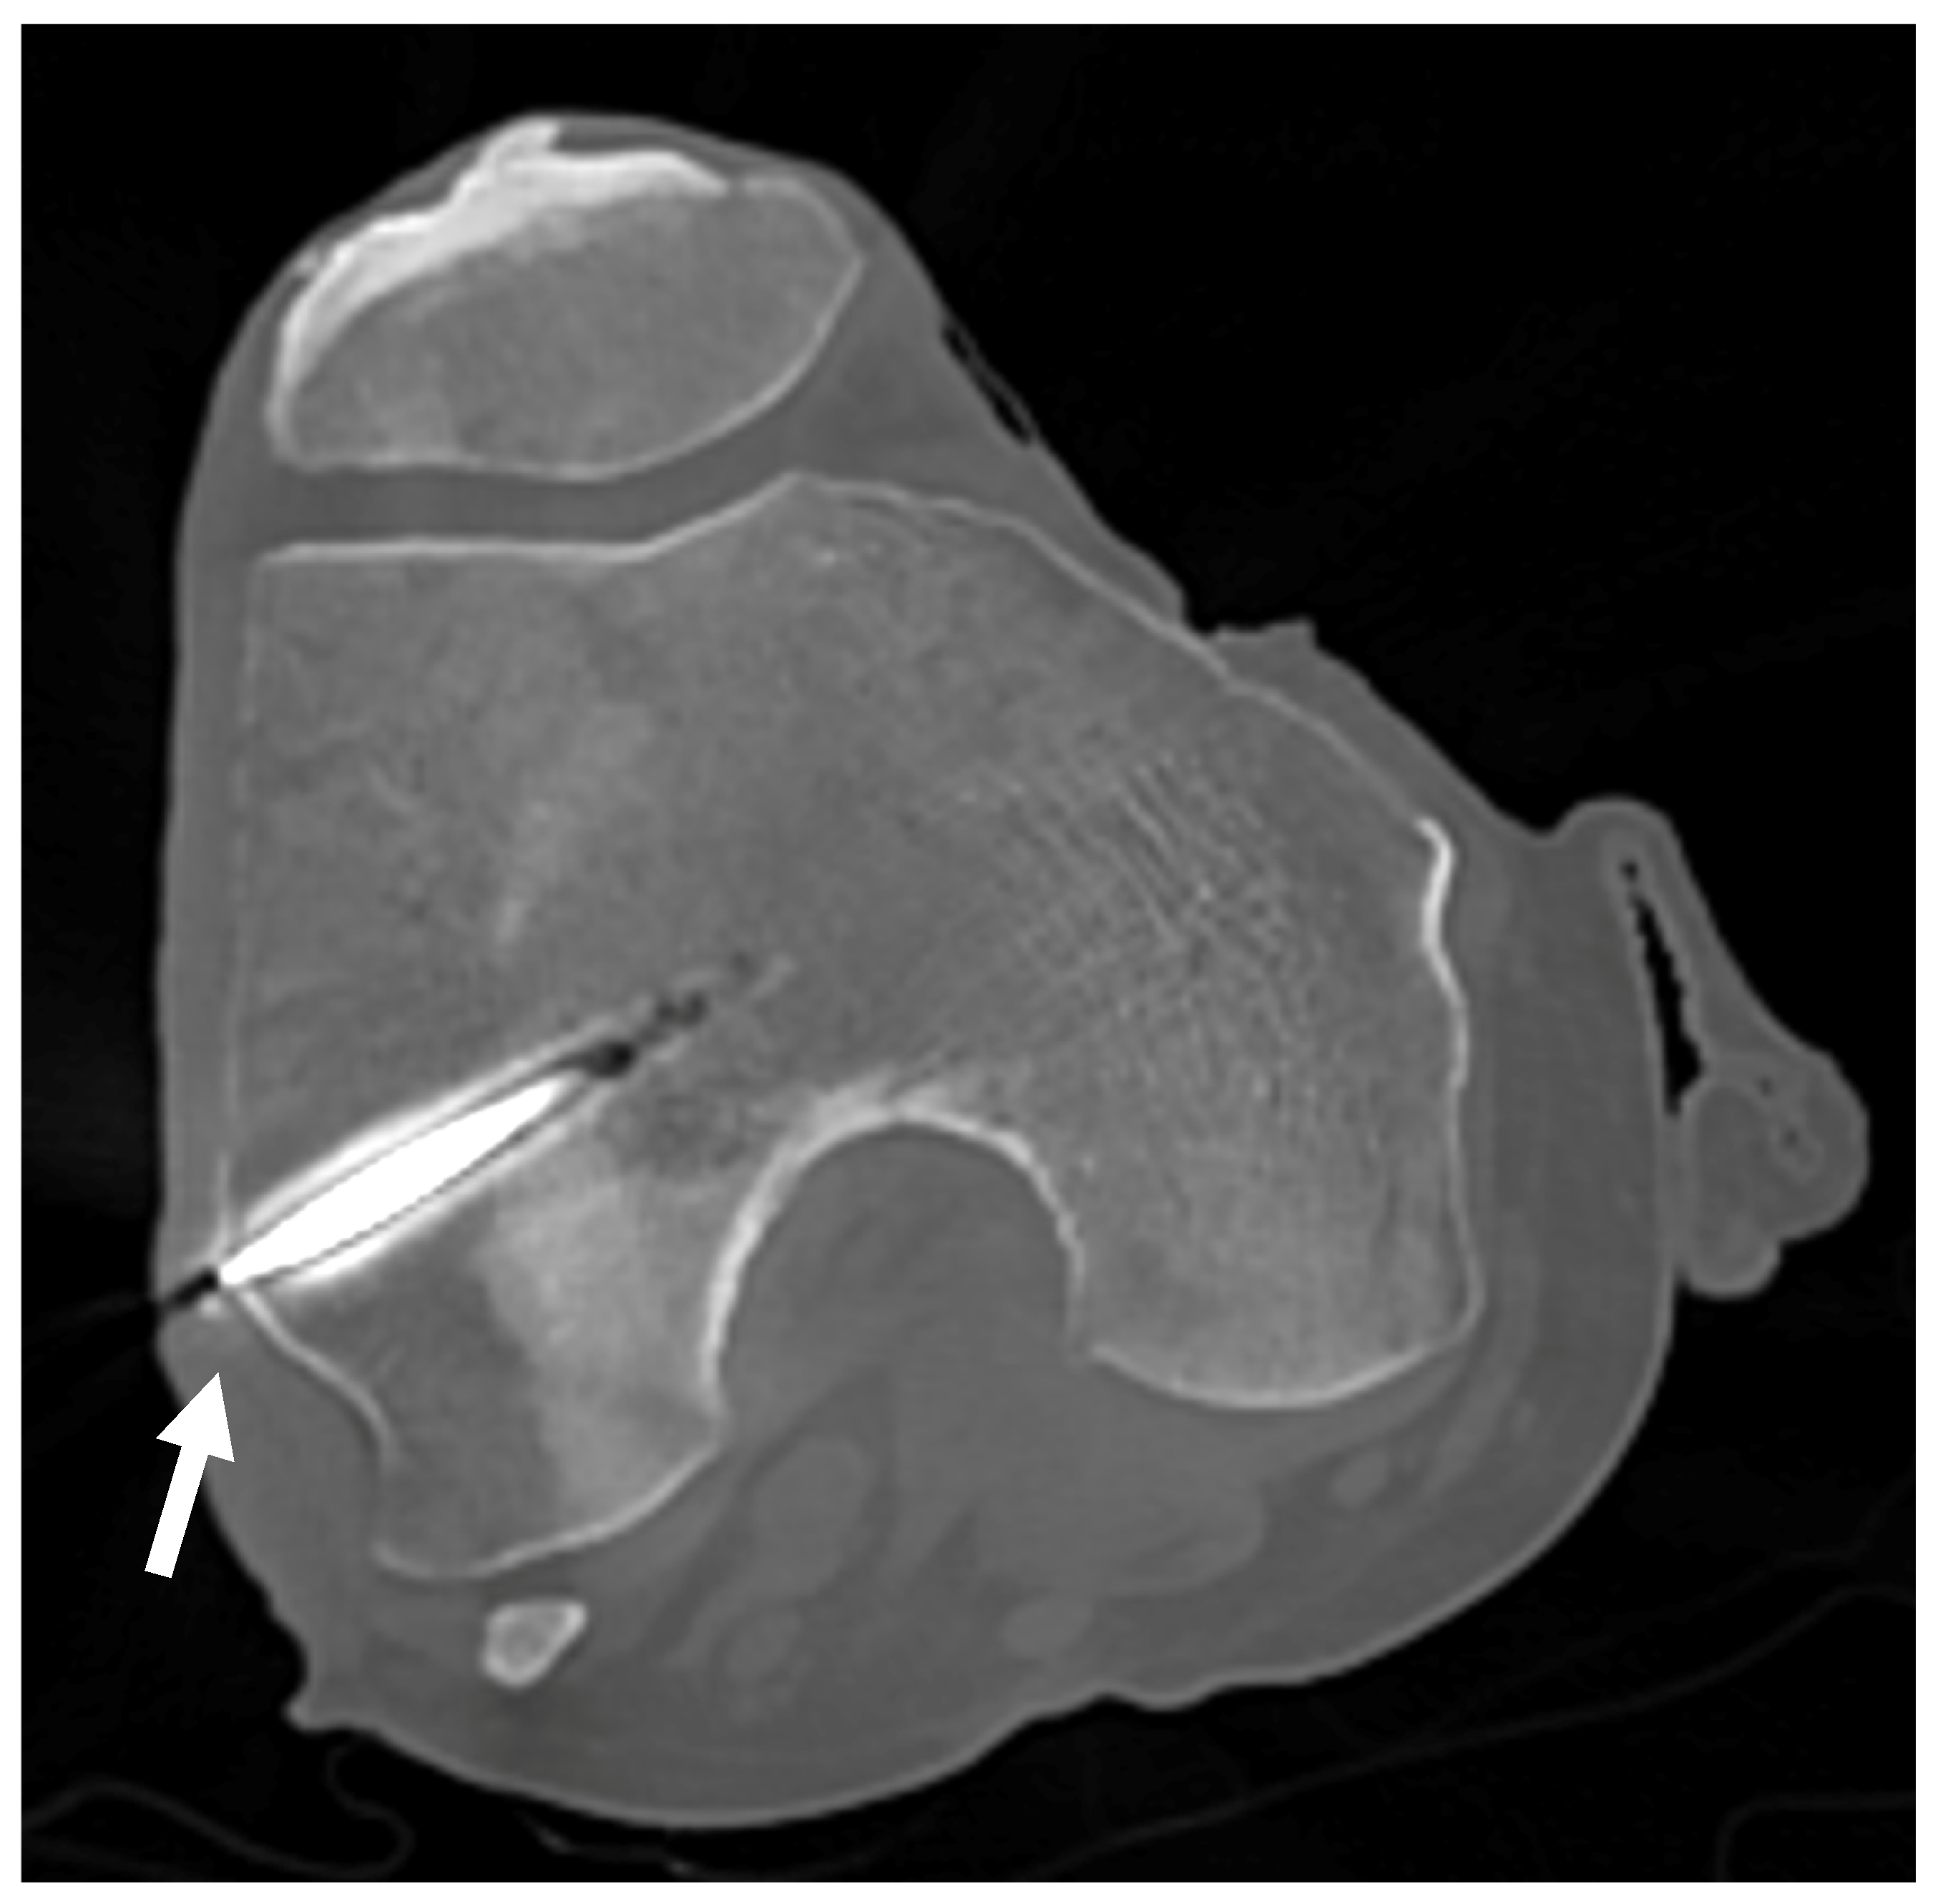

In the first set of samples (knees 1 to 4), the trocars were correctly placed towards the LFE, except for the left leg of knee 1, which showed a distance of 6.7 mm between the tip of the wire and the apex of the LFE as measured on the CT scan coronal view (Figure 9). The results are reported in Table 3.

Figure 9.

CT scan of knee 1. CT scan used to confirm proper positioning of the trocar for knees 1 to 4. The white arrow points to the LFE, confirming alignment with the targeted anatomical structure.

Table 3.

Distance between the tip of the trocar and the apex of LFE, measured by CT scan.

No formal intra operator reliability assessment was conducted however, guide wire positioning was retrospectively verified. In the first four knees, CT imaging was used retrospectively to verify trocar positioning due to an unexpected failure of the fluoroscopy unit. Once fluoroscopy was operational, it was used intraoperatively for the remaining knees. The use of both imaging modalities ultimately reinforces the applicability of our protocol, as it demonstrates that trocar positioning can be reliably assessed using either CT or fluoroscopy, depending on equipment availability in laboratory settings. All procedures were performed by a fellowship-trained orthopedic surgeon specializing in sports medicine. In one of the CT-evaluated knees, a misalignment greater than 6 mm was observed. This was on the first specimen, and the surgeon indeed noted a slight glide of the tip of the pin at insertion. A more careful insertion technique was then used to avoid the same mistake. However, the light-defined point used for measurements remained stable, and the average relative displacement between 0° and 30° of flexion was therefore unaffected. The use of fluoroscopy gives direct inputs on proper pin placement on the antero-posterior (AP) view and may be a less expensive technique. On the other hand, since the LFE is impossible to locate from the lateral view, it leaves only the AP view to locate the projection of the contour of the LFE. This may lead to undetected anterior or posterior placement of the wire. Both techniques therefore have their limitations. The best scenario would be to insert the wire, use the CT scan to validate the proper position, and then bring the cadaveric knee back to the lab to move on with the measurements. In our setting, this was not practicable.